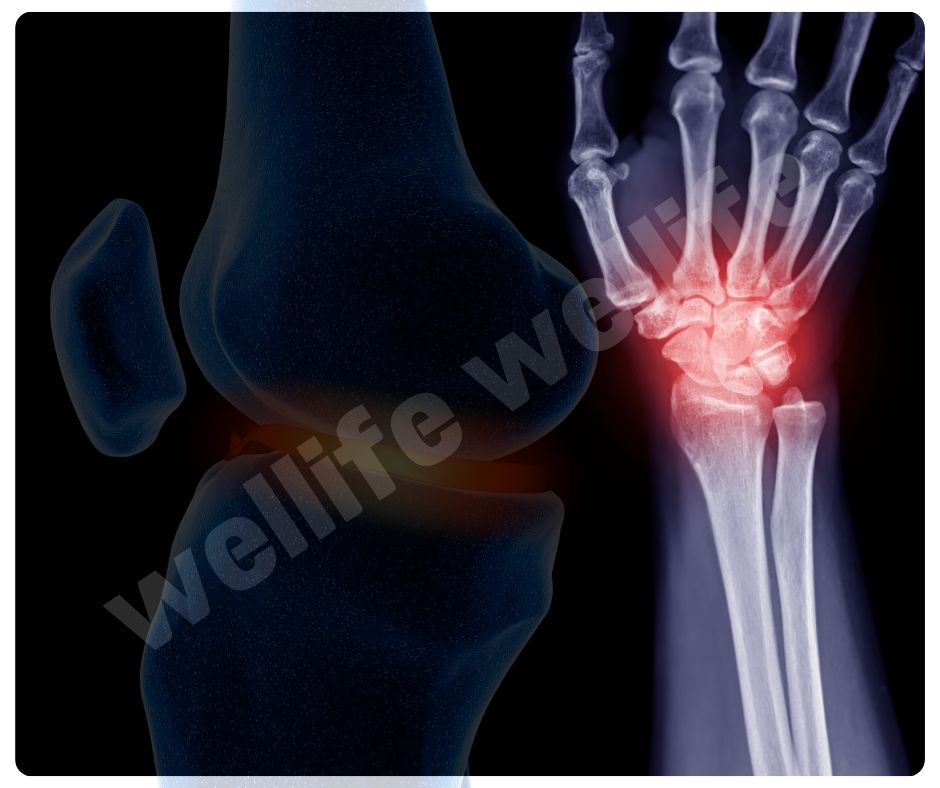

콘드로이친은 연골의 중요한 구성 성분으로, 관절을 보호하고 부드럽게 움직이게 도와주는 역할을 해요. 주로 동물의 연골에서 추출되며, 관절염 환자들이 많이 찾는 보충제랍니다.

콘드로이친 효능 중 가장 대표적인 것은 골관절염(Osteoarthritis) 완화입니다. 골관절염은 연골이 닳아 없어지면서 통증과 강직을 유발하는 만성 질환인데요, 콘드로이친은 연골 손상을 줄이고 증상을 완화하는 데 효과적이에요.

- 연골 보호 및 재생: 콘드로이친은 연골의 구조를 유지하고, 손상된 연골의 재생을 돕는 효능이 있습니다.

- 통증 완화: 관절 통증을 줄이고, 관절의 기능을 개선하는 데 도움을 줍니다.